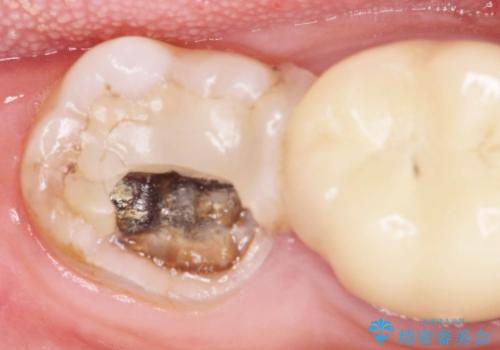

インレー下に再発した虫歯 セラミッククラウンによるやり替え